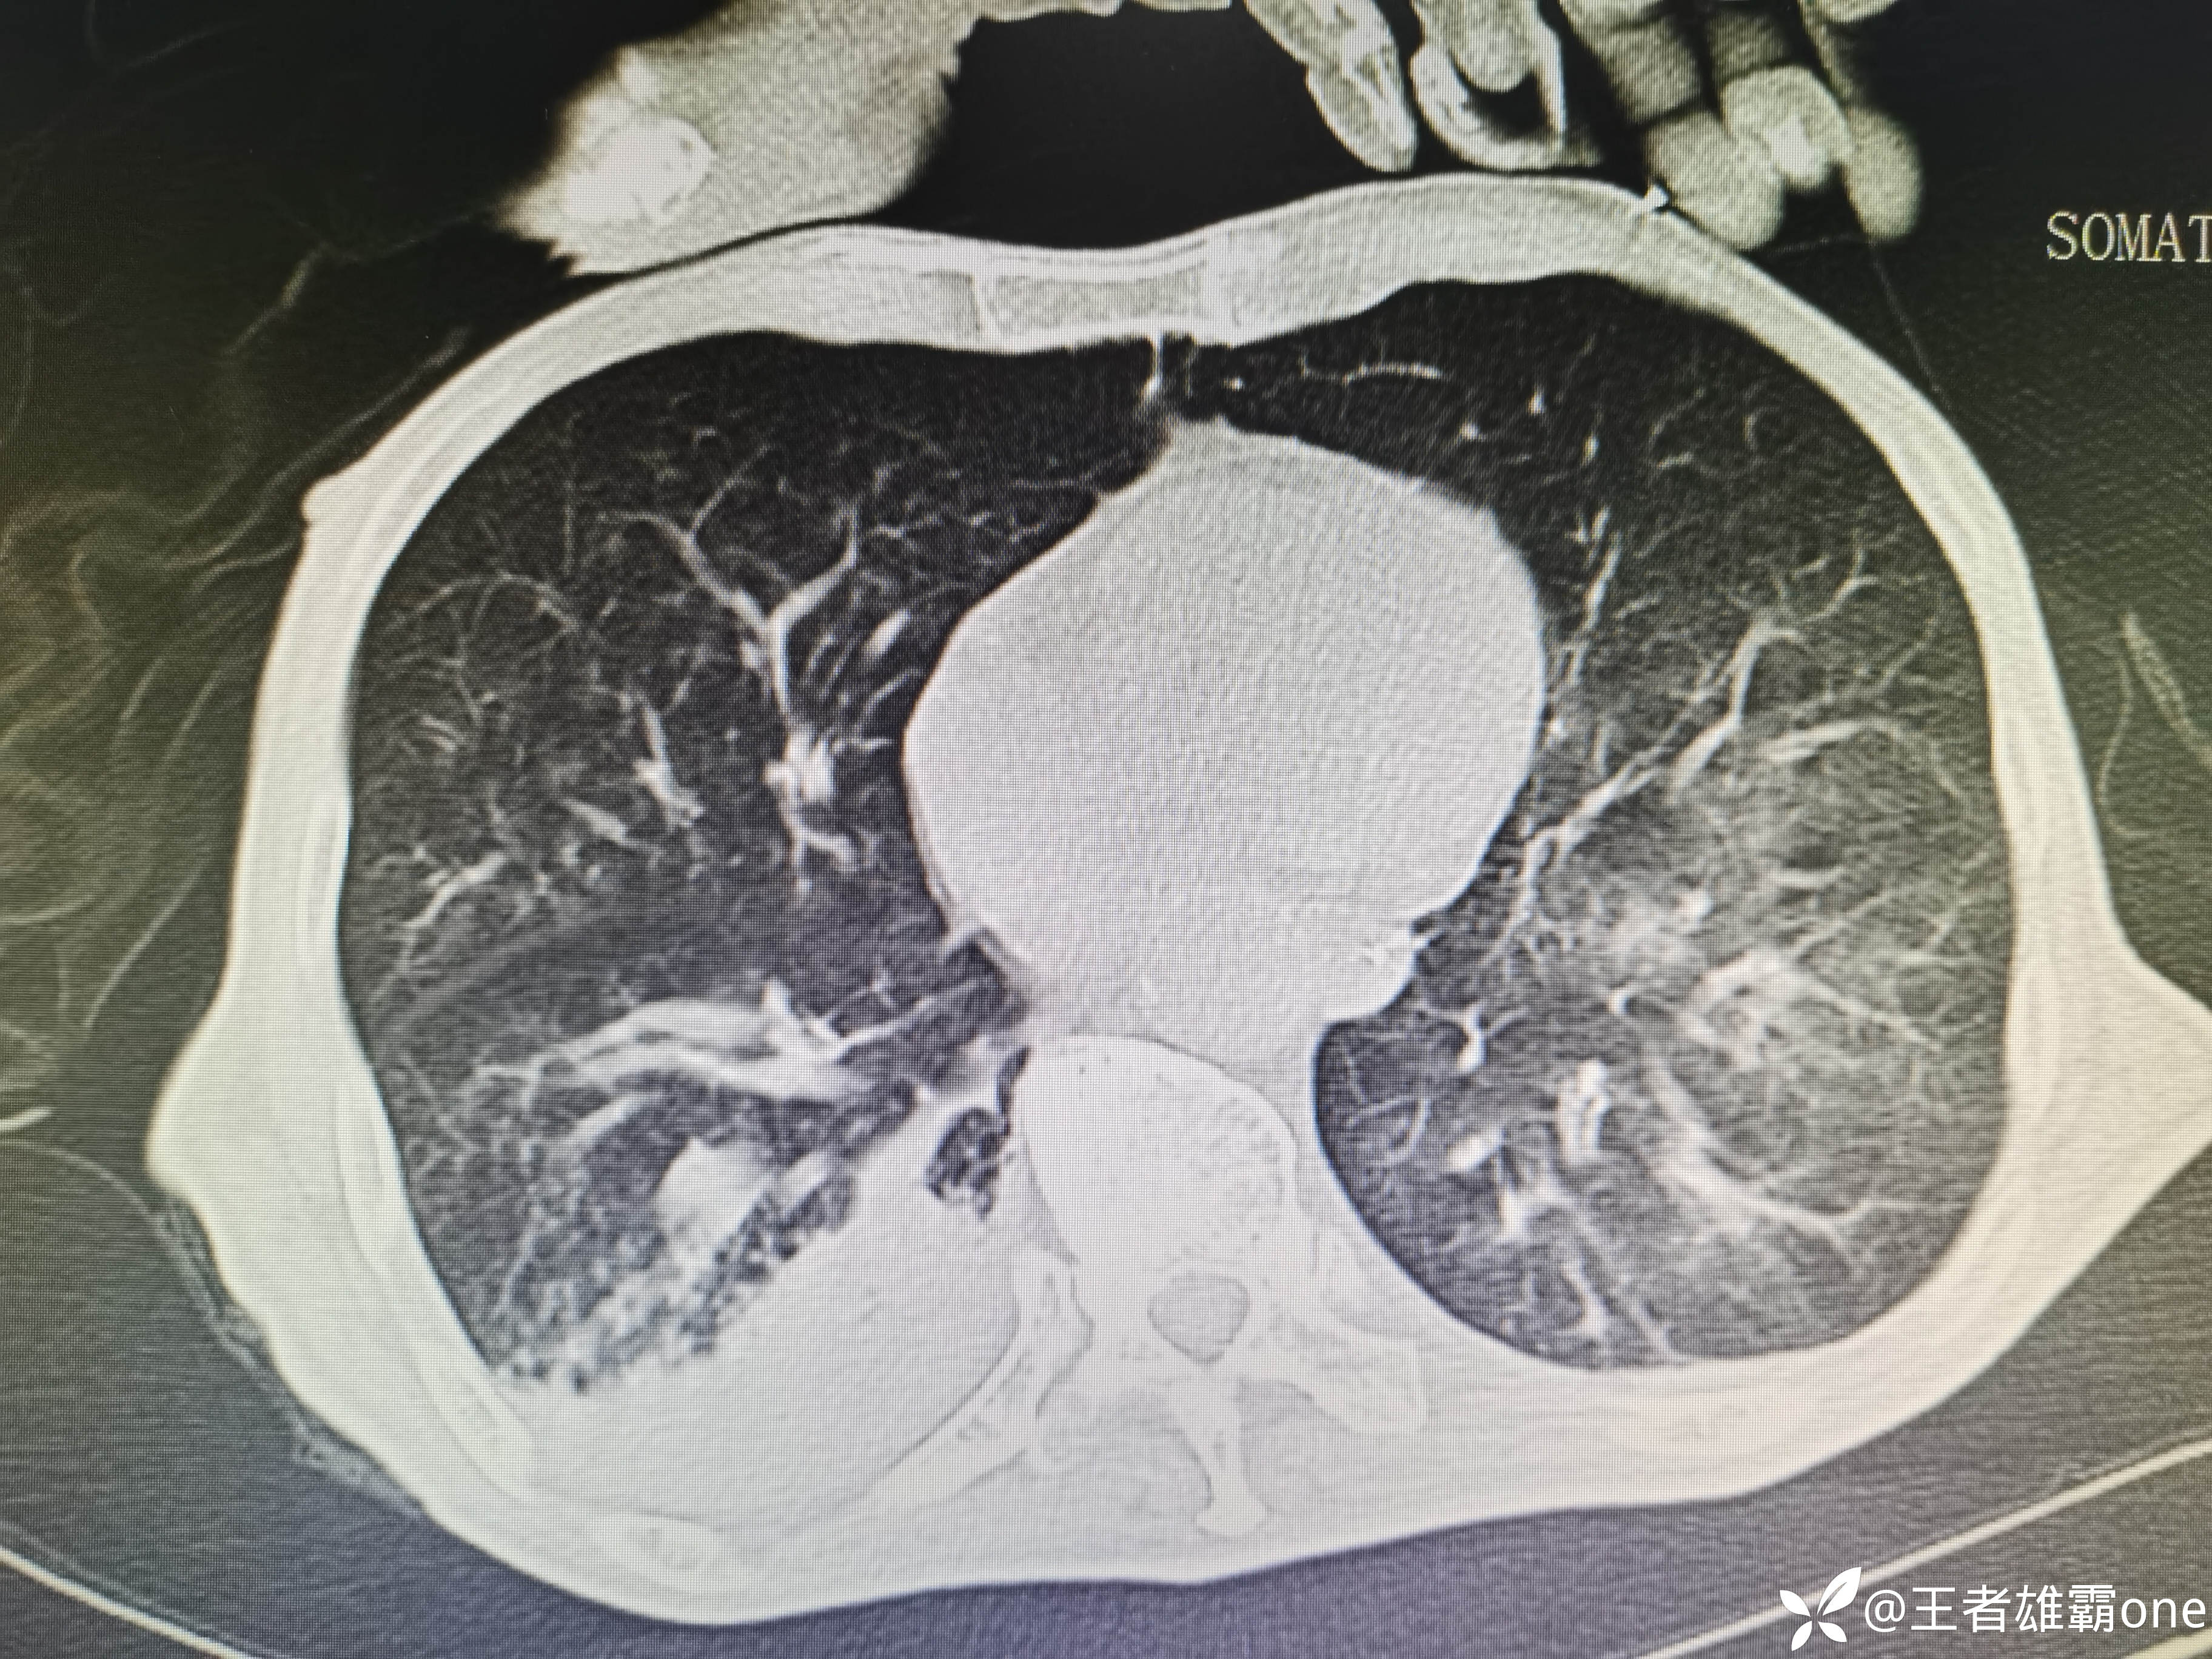

入院时胸部CT:

具体图片: